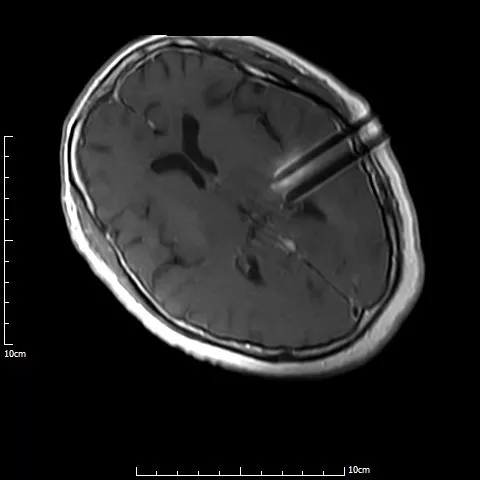

3D打印模板术中定位

介入手术治疗中,

磁共振实时引导技术保证介入手术过程在可视化下连续性完成

手术过程仅半小时,先对满女士进行局麻,然后在1.0T开放式介入磁共振监控及3D打印模板引导下,

李成利主任将4根磁共振兼容性穿刺针平行穿刺至肿瘤病变既定位置,根据近距离放疗计划植入I125放射性粒子,

术中磁共振显示,4根穿刺针平行准确穿刺至病灶内